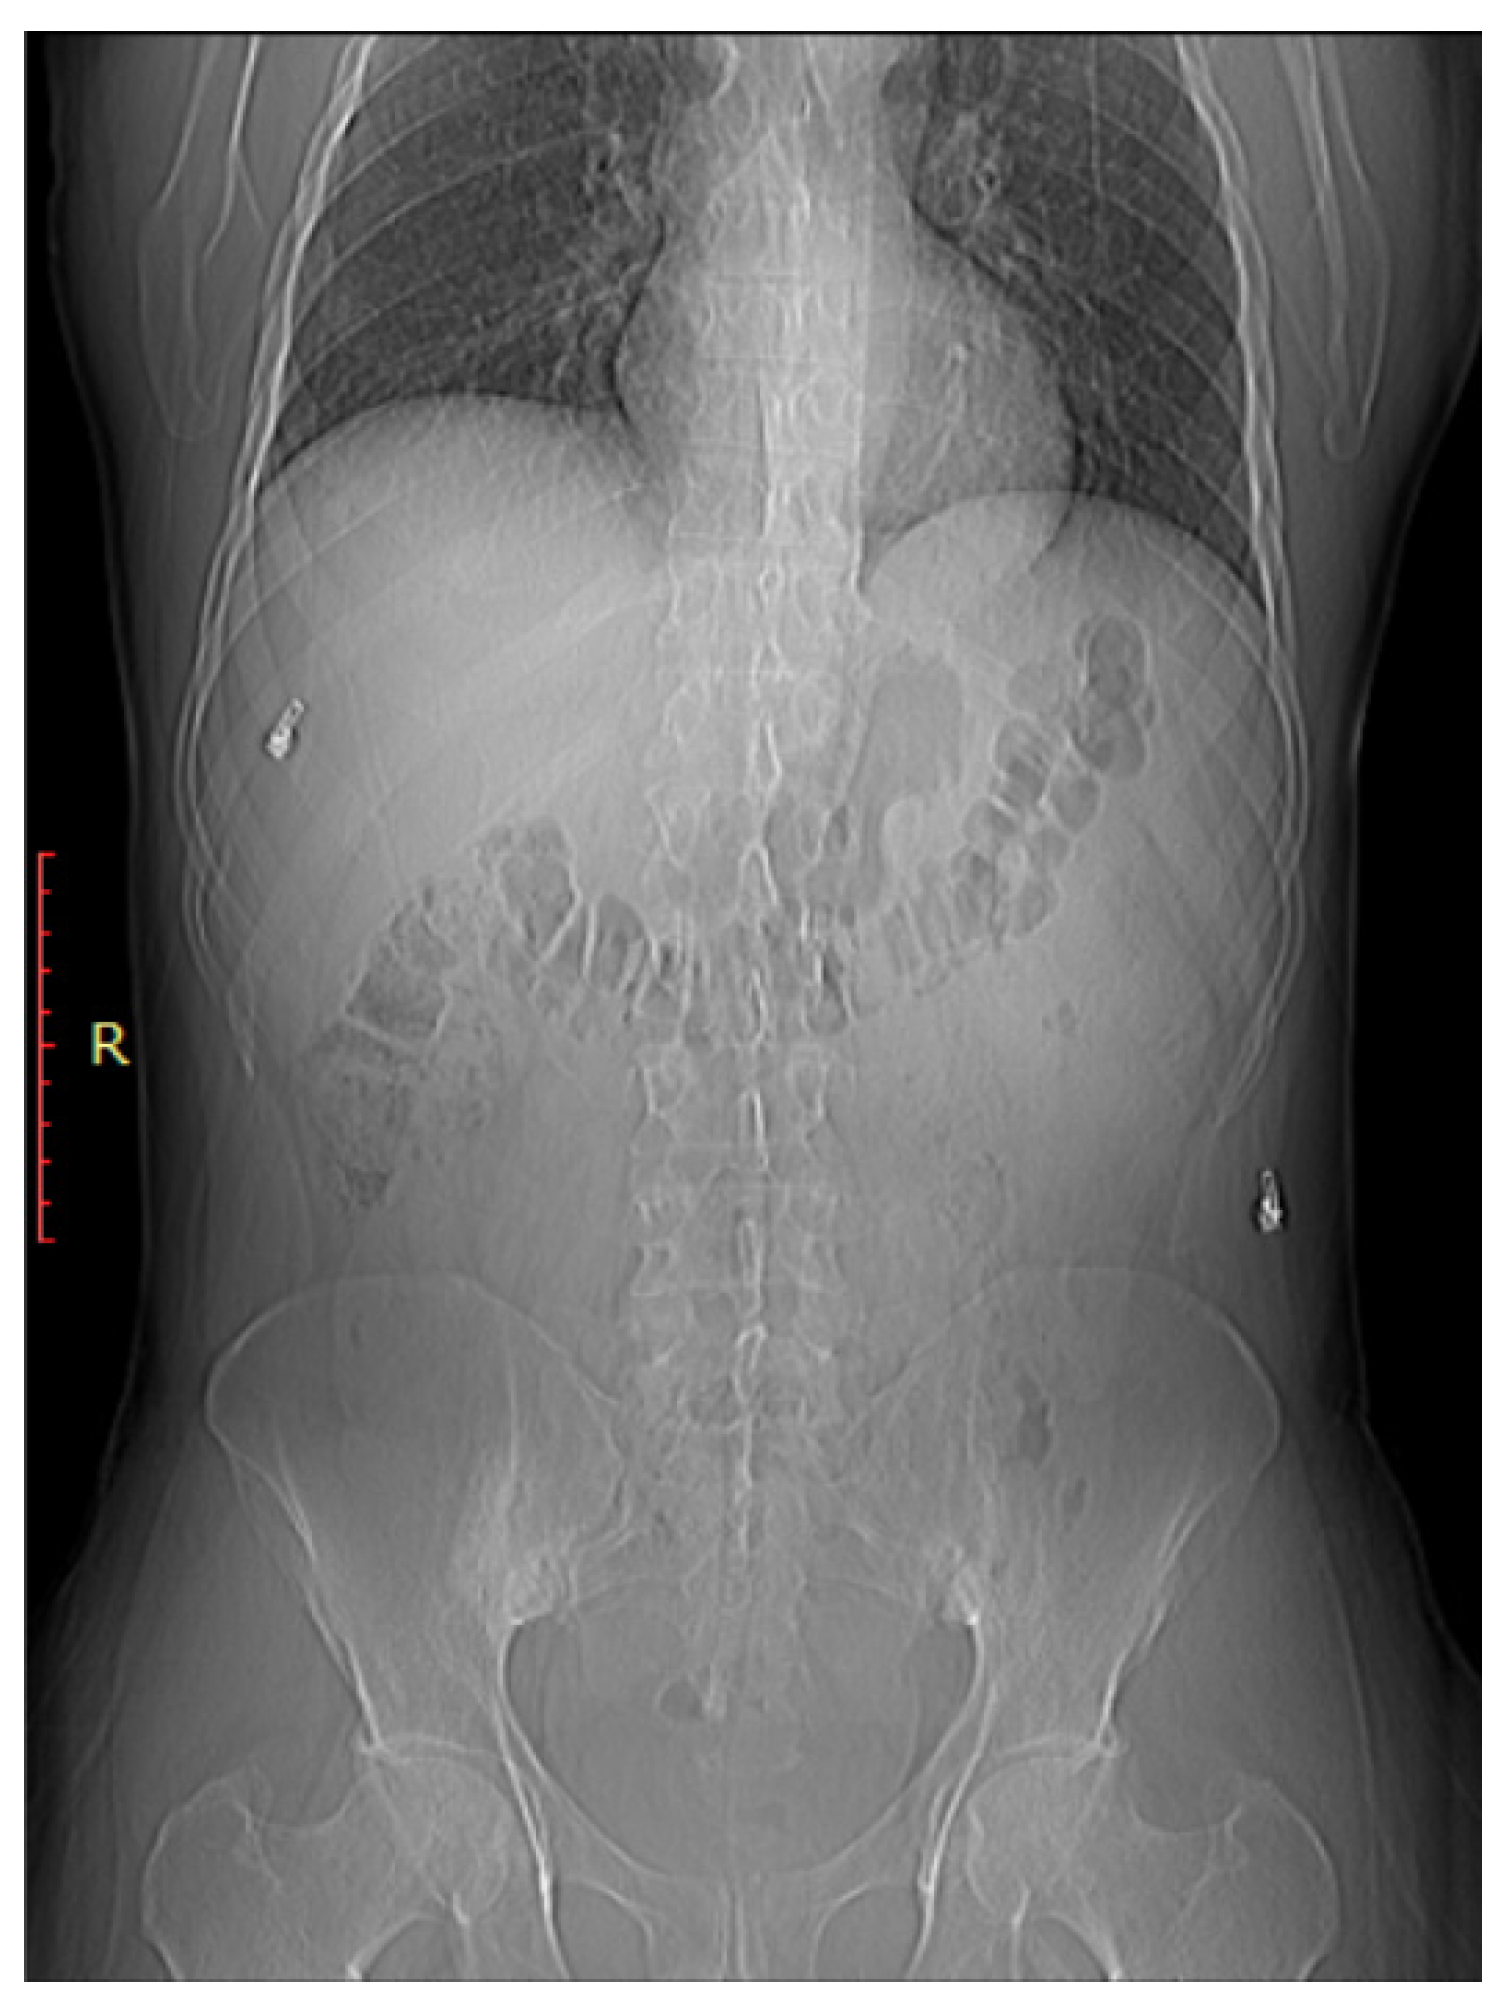

Figure 3.

Bilateral sacroiliitis. X-ray for a 41-year-old male presenting with Rt sciatica showing irregularity and sclerosis of both sacroiliac joints is more evident on the right.

In severe cases or in advanced stages of ankylosing spondylitis (a type of inflammatory arthritis), the sacroiliac joints may become completely fused or ankylosed. On X-ray, this presents as a loss of joint space and a bony bridge or fusion between the sacrum and ilium [1].

As shown in Figure 2, early sacroiliitis may show subtle erosions at the joint margins [44]. These erosions are typically irregular and may appear as small, well-defined areas of bone loss [44]. As the inflammation progresses, the joint may become more sclerotic, leading to increased bone density in the SI joint [45]. Progressive inflammation can lead to narrowing of the SIJ space, indicating joint damage and dysfunction As shown in Figure 3, early sacroiliitis may show subtle erosions at the joint margins [44]. These erosions are typically irregular and may appear as small, well-defined areas of bone loss [44]. As the inflammation progresses, the joint may become more sclerotic, leading to increased bone density in the SI joint [45]. Progressive inflammation can lead to narrowing of the SIJ space, indicating joint damage and dysfunction [1]. In addition, changes in the subchondral bone, including irregularities, sclerosis, and erosions, are common features of sacroiliitis [46].